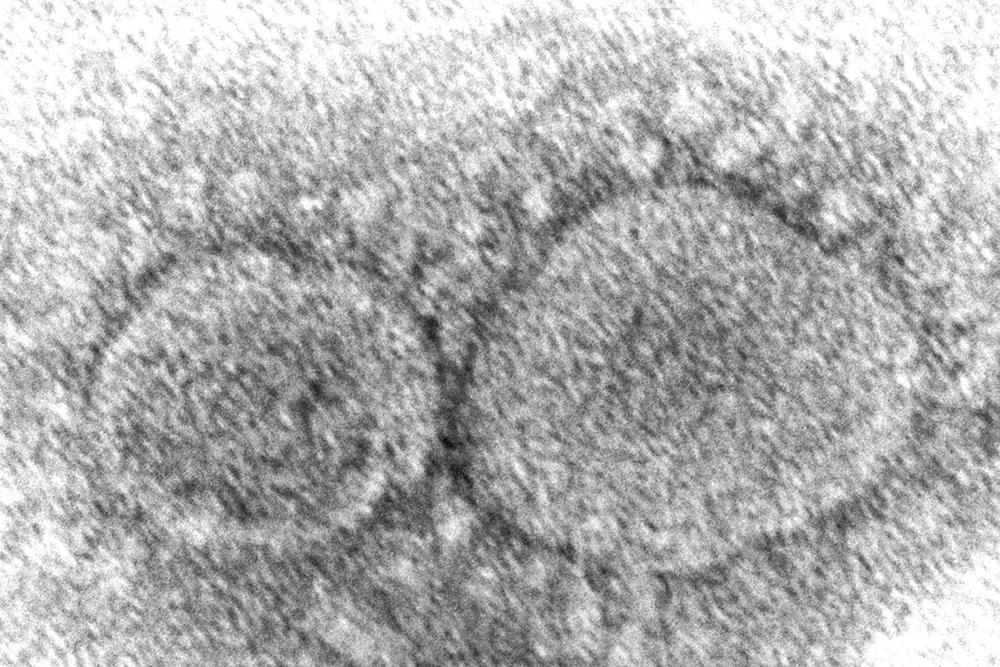

COVID-19 vaccines work by triggering production of antibodies that recognize and attack the spike protein that coats the coronavirus, and many are made with new technology flexible enough for easy updating. The Pfizer and Moderna vaccines are fastest to tweak, made with genetic instructions that tell the body to make harmless copies of the spike protein — and that messenger RNA can be swapped to match new mutations.